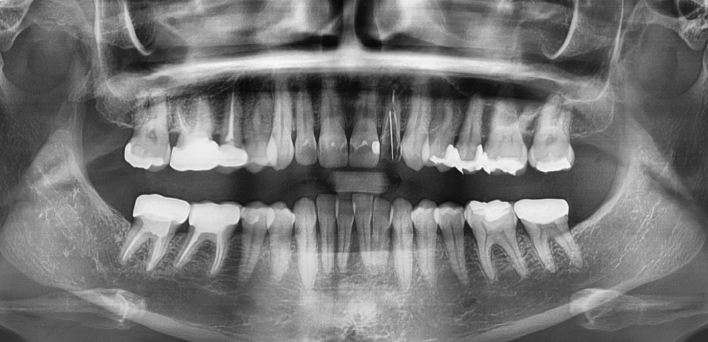

임플란트 Before & After

The seoul dental clinic

※ 더서울치과의원은 의료법을 준수하며 위 케이스는 실제 환자의 동의를 얻은 사례로 치료 전, 후가 동일한 환경에서 촬영되었습니다.

환자 케이스에 따라 부작용이 발생할 수 있습니다. 이 부분은 의료진의 충분한 상담과 체크를 통해 예방하고 줄일 수 있습니다.

[임플란트 부작용] 수술 후 관리가 소홀할 경우 출혈, 주위염 등의 부작용이 발생할 수 있어 구강 위생을 철저히 유지하고, 정기적인 검진을 통해 상태를 점검하는 것이 중요합니다.